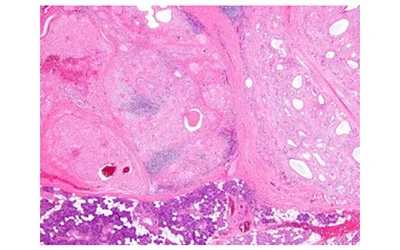

Tack and Permute-NUT Sinonasal Carcinoma

Anubha Bajaj. 22(10): 01-05.

The Wiry Wen-Sclerosing Polycystic Adenoma

Anubha Bajaj. 22(10): 01-04.